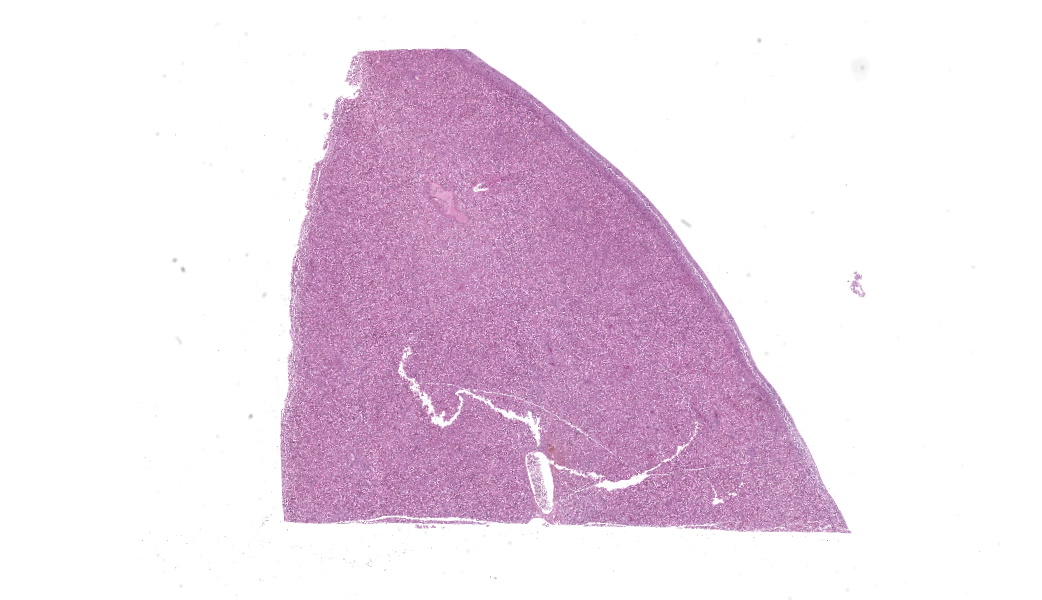

Gross Pathology: The liver was enlarged and diffusely dark red. The spleen was moderately enlarged.Laboratory Results:

Round hematopoietic tumor cells strongly infiltrated the hepatic blood vessels and sinusoids. The hepatic sinusoids were diffusely expanded by tumor cell infiltration, with fewer normal erythrocytes and enlarged Kupffer cells which sometimes contained cellular debris. Most hepatocytes were shrunken. A few granulocytes were also found in the hepatic sinusoid. Small foci of granulocytic cells at different nuclear maturation stages were present around some hepatic triads. Tumor cells appeared round, oval, or polygonal in shape with a distinct cell border, amphophilic cytoplasm, anisocytosis, and anisokaryosis. Some tumor cells contained perinuclear pale areas known as halos. The nucleus was round and hyperchromatic to pale, with one or two large nucleoli and coarsely clumped chromatin. Some binuclear tumor cells were also observed. There was significant mitosis and karyorrhexis of tumor cells. The cytoplasmic eosinophilic granules that are characteristic to myelocytic lineage cells were not present in tumor cells.Immunohistochemical analysis revealed that tumor cells consistently exhibited cytoplasmic staining of hemoglobin antigen, with variable staining intensity, faint to strong, depending on the tumor cell. Hemoglobin was also detected in normal erythrocytes. Tumor cells were negative for CD3 (T cell marker), BAFF-R (B cell marker), and Iba-1 (macrophage/monocyte marker). Enlarged Kupffer cells were positive for Iba-1.

Tumor cells were observed in other organs, but only in the blood vessels. Some thrombi composed of necrotic tumor cells and fibrin were also observed in the vessels. The bone marrow was not histologically examined.